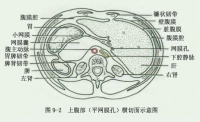

腹腔横断面(通过网膜孔)